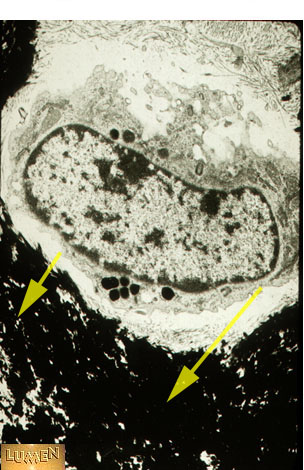

What is this substance?

Answer

apatite (CaPO4)